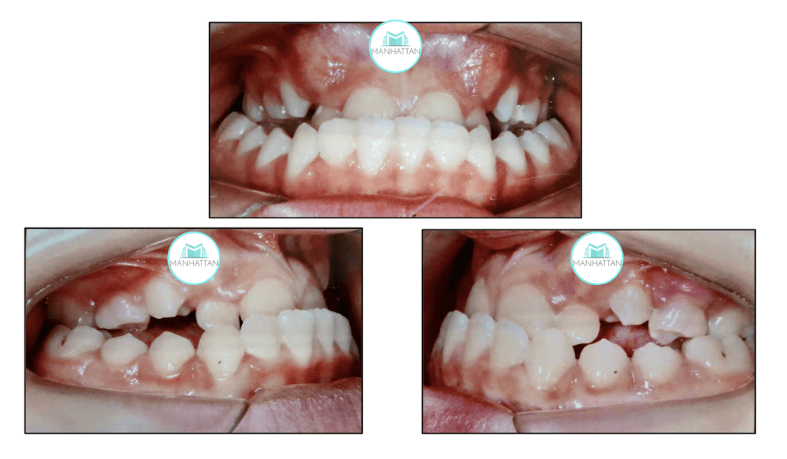

O diagnóstico inicial

Na primeira consulta, percebemos que a paciente tinha mordida cruzada na frente e nos lados, um sorriso estreito e um queixo mais projetado, deixando seu rosto com aspecto côncavo (como se a parte do meio do rosto fosse mais "para trás"). Apesar da pouca idade, era fundamental começar o tratamento o quanto antes para evitar que o problema se agravasse.